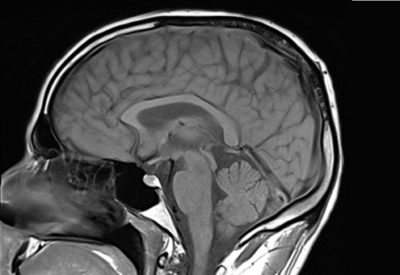

Hochwertige MRT-Untersuchung für maximale Diagnosesicherheit

Dann sind Sie bei uns richtig! Wir bieten Ihnen ein erfahrenes und spezialisiertes Ärzteteam, das MRT-Untersuchungen mit moderner Gerätetechnik durchführt. Unsere MRT-Untersuchungen sind optimiert und liefern hochauflösende Bilder, die eine maximale Diagnosesicherheit bieten.

Hochwertige MRT-Untersuchung für maximale Diagnosesicherheit

Dann sind Sie bei uns richtig! Wir bieten Ihnen ein erfahrenes und spezialisiertes Ärzteteam, das MRT-Untersuchungen mit moderner Gerätetechnik durchführt. Unsere MRT-Untersuchungen sind optimiert und liefern hochauflösende Bilder, die eine maximale Diagnosesicherheit bieten.